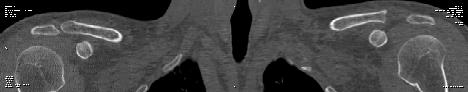

[Ortho] Остеолиз ключицы

Вот как то так выглядят сканыв аксиальной проекции (по отдельности правый и левый суставы) и MPR реконструкция обоих

Вложение не в текстовом формате было извлечено…

Имя     : B CT reco.jpg

Тип     : image/jpg

Размер  : 7652 байтов

Описание: отсутствует

Url     : http://weborto.net:8080/pipermail/ortho/attachments/20120616/75850712/attachment-0003.jpg